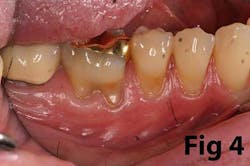

Gingival recession is the result of loss of alveolar bone and tissue, specifically AG. A high number of recession cases result in less than the minimum required amount of AG. (Fig. 4) Similarly, following tooth extraction or long-standing edentulism (without bone preservation), loss of alveolar dimension is accompanied with diminishing AG. (Fig. 5)Note: specific cases may also be attributed to gingival biotype and genetic predisposition.